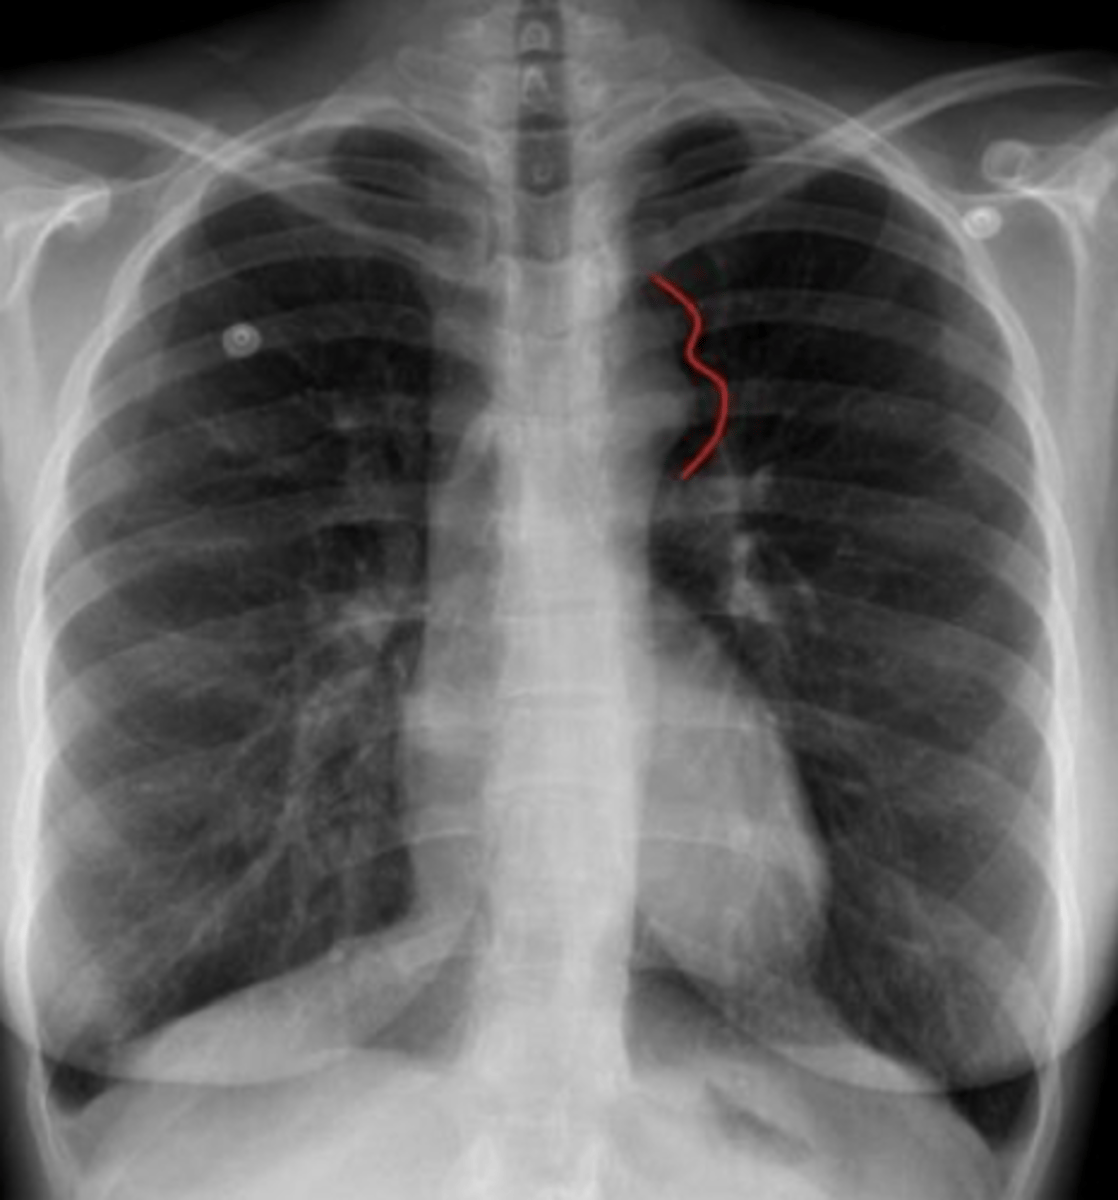

What is the finding on the back of the card?

coarctation of aorta

<p>coarctation of aorta</p>